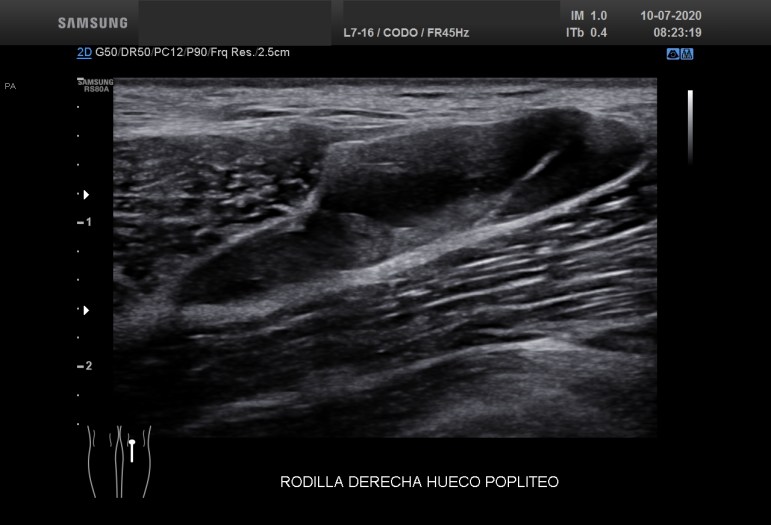

Compara estos dos quistes de Baker, si los miras bien son prácticamente iguales. Hay una diferencia muy importante entre tanta igualdad…uno es normal, el otro es patológico. Las tres últimas imágenes, 5 a 7, corresponde a un quiste de Baker infantil, por tanto se considera un hallazgo que puede ser normal para estas edades, esta figura en a edad adulta es siempre patológica y en relación con artrosis y cambios degenerativos de la articulación.

Por tanto, en la infancia se desconoce la forma clara el mecanismo por el que se produce. Podría estar relacionado con el desarrollo de la rodilla, pero a diferencia del adulto, su presencia no refleja ningún tipo de alteración intraarticular de la rodilla.

Imágenes idénticas de figuras patológicas que en el caso de la edad infantil no revisten más importancia y solo necesitan control. La exeresis de estos quistes no elimina la posibilidad de que se reproduzcan.